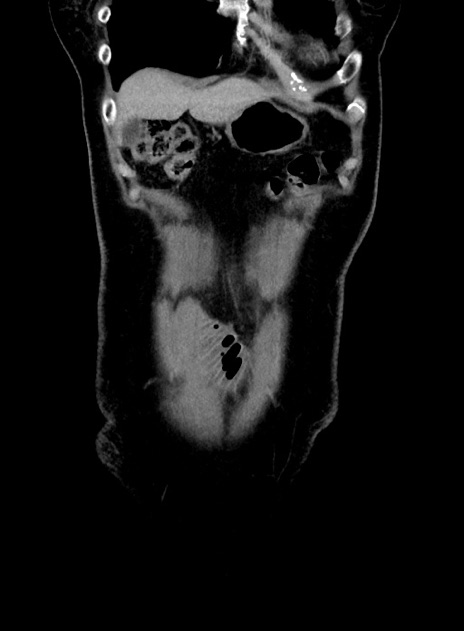

横断像

【症例】 60歳代女性

【主訴】むかつき、みぞおちの痛み

【現病歴】3日前よりむかつきがあり、食事がとれない。

【既往歴】糖尿病

【身体所見】発熱なし、心窩部圧痛軽度あるも、腹膜刺激症状なし。

【データ】WBC 7400、CRP 1.92